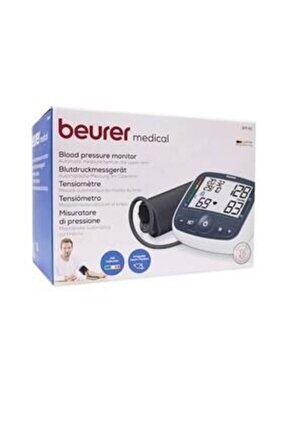

Ölçüm CihazıBm 40 Onpack Tansiyon

8.818,92 TL